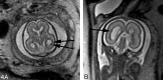

Fetal MR imaging is an increasingly available technique used to evaluate the fetal brain and spine. This is made possible by recent advances in technology, such as rapid pulse sequences, parallel imaging and advances in coil design. This provides a unique opportunity to evaluate processes that cannot be approached by any other current imaging technique and affords a unique opportunity for studying in vivo brain development and early diagnosis of congenital abnormalities inadequately visualized or undetectable by prenatal sonography. This 2-part review summarizes some of the latest developments in MR imaging of the fetal brain and spine and its application to prenatal diagnosis. This first part discusses the utility, safety, and technical aspects of fetal MR imaging, the appearance of normal fetal brain development, and the role of fetal MR imaging in the evaluation of fetal ventriculomegaly. The second part focuses on additional clinical applications of fetal MR imaging, including suspected abnormalities of the corpus callosum, malformations of cortical development, and spine abnormalities.